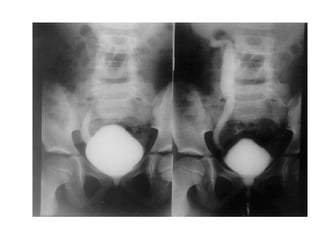

REFLUXO VESICOURETERAL

 Fluxo retrógrado anormal de urina da bexiga

para os ureteres.

 Pode ser primário ou secundário.

 Predispõem a infecções renais / pielonefrite.

 Associada a cistite leva a fibrose renal.

UROPATIA OBSTRUTIVA

 Anormalidades estruturais ou funcionais do sistema

urinário que obstruem o fluxo normal de urina.

 ↓ fluxo urinário  hidronefrose – dilatação da

pelve renal devido retenção  destruição do

parênquima renal.

 Pode ser congênita ou adquirida, uni ou bilateral,

completa ou incompleta.

 Pode ocorrer em qualquer nível do trato urinário.

 Freqüente em meninos.